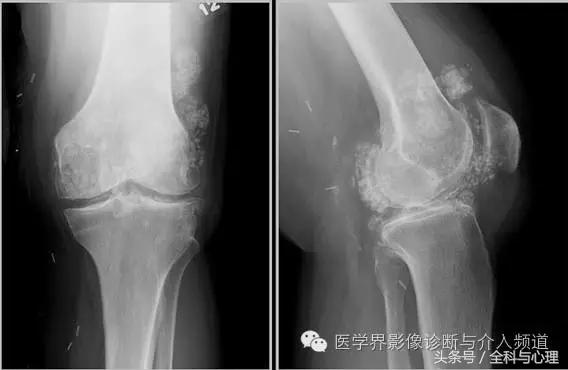

3、CPPD(焦磷酸钙沉积症)相关性钙化

CPPD(焦磷酸钙沉积症)